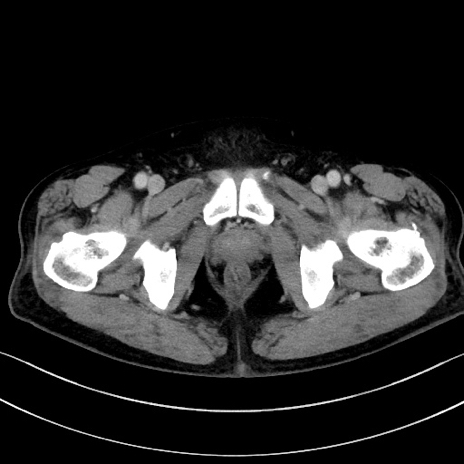

冠状断像

【症例】70歳代男性

【主訴】腹痛

【現病歴】今朝から腹痛あり。全体的に痛い。特に左上の方。排ガスが今日はない。冷や汗が出る。

【既往歴】直腸癌術後

【身体所見】左側腹部〜上腹部に圧痛あり。腹膜刺激症状明らかなではない。軽度反跳痛。左下腹部に術後瘢痕あり。

【データ】WBC 7700、CRP 0.02